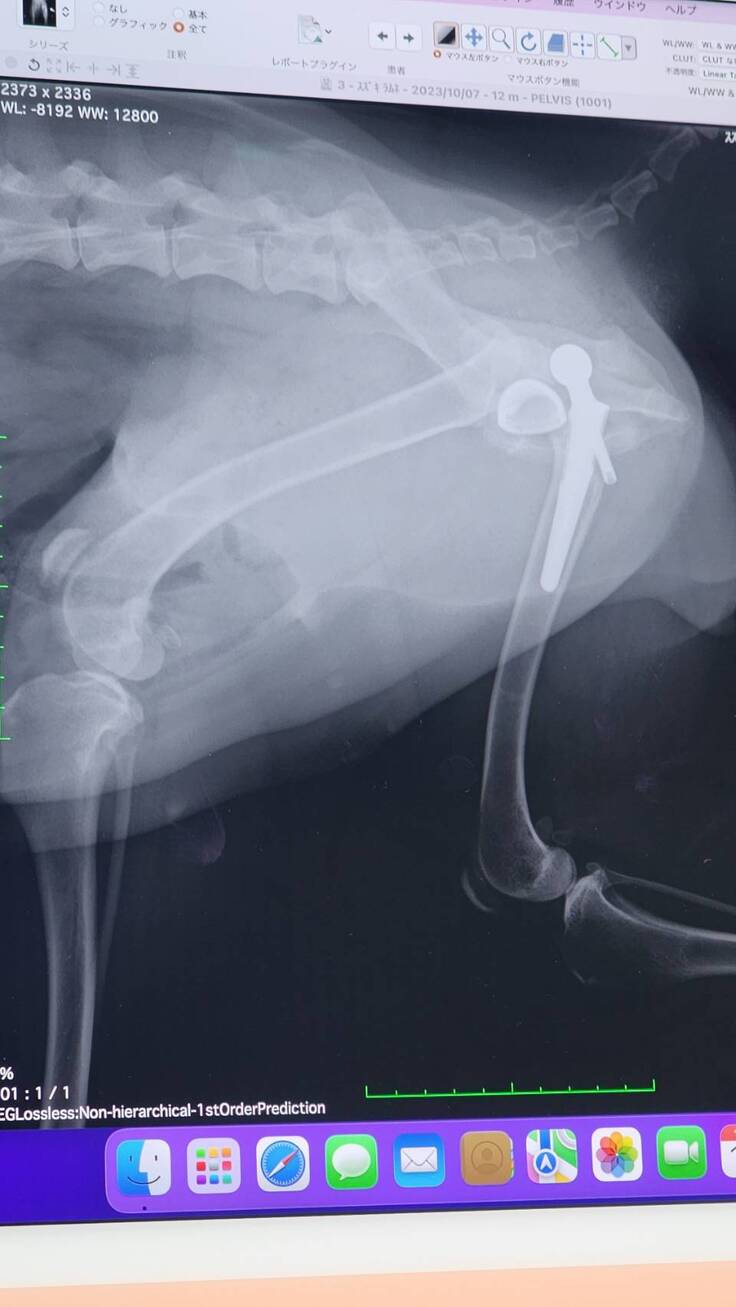

退院予定日の2日前に病院から連絡が入り、人工股関節が脱臼してしまっていると報告を貰いました。

緊急で昨日再手術があり本日10/13が退院予定日でしたが、病院で現状と今後の説明がありました。

もともと亜脱臼状態で生活していたため筋肉もそのように作られており人工股関節に違和感がありはずれてしまった。さらに人が好きすぎて看護師さんを見ただけでもはしゃいでおりそのタイミングで外れてしまった。いくつかの過程を聞き最後に。。。

1・再手術のためさらに2週間入院 退院予定早くて10月末